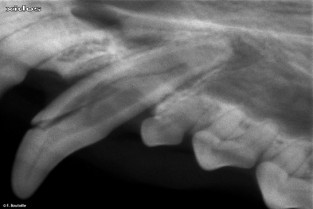

Les premiers jours visent à apprendre les compétences fondamentales à la mise en place d’un service en dentisterie : utilisation de l’instrumentation, obtention de clichés radiographiques ad hoc , réalisation d’extractions chirurgicales chez le Chien et le Chat et correction des troubles de l’occlusion chez le Lapin. Par la suite sont abordés l’interprétation des images radiolo- giques, les affections du parodonte et de la pulpe dentaire, la gestion des stomatites, les techniques de restauration dentaire et les premiers pas en orthodontie et chirurgie maxillo-faciale. Cette formation se compose de 36 heures dédiées aux connaissances essentielles associées à 74 heures de mises en pratiques se déroulant dans des conditions de travail idéales.